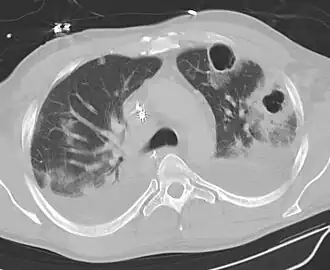

CT Thorax - beeld van pneumonie met verscheidene longabcessen, 2 cavernes en effusies dorsaal en rond de cavernes